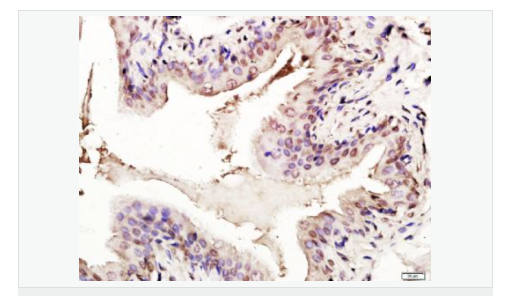

| 產(chǎn)品應(yīng)用 | WB=1:1000-2000 ELISA=1:1000-5000 IHC-P=1:100-500 IHC-F=1:100-500 Flow-Cyt=1ug/Test ICC=1:100-500 IF=1:100-500 (石蠟切片需做抗原修復(fù)) not yet tested in other applications. optimal dilutions/concentrations should be determined by the end user. |

| 產(chǎn)品介紹 | p53, a DNA-binding, oligomerization domain- and transcription activation domain-containing tumor suppressor, upregulates growth arrest and apoptosis-related genes in response to stress signals, thereby influencing programmed cell death, cell differentiation, and cell cycle control mechanisms. p53 localizes to the nucleus, yet can be chaperoned to the cytoplasm by the negative regulator, MDM2. MDM2 is an E3 ubiquitin ligase that is upregulated in the presence of active p53, where it poly-ubiquitinates p53 for proteasome targeting. p53 fluctuates between latent and active DNA-binding conformations and is differentially activated through posttranslational modifications, including phosphorylation and acetylation. Mutations in the DNA-binding domain (DBD) of p53, amino acids 110-286, can compromise energetically-favorable association with cis elements and are implicated in several human cancers. Function: [FUNCTION] Acts as a tumor suppressor in many tumor types; induces growth arrest or apoptosis depending on the physiological circumstances and cell type. Involved in cell cycle regulation as a trans-activator that acts to negatively regulate cell division by controlling a set of genes required for this process. One of the activated genes is an inhibitor of cyclin-dependent kinases. Apoptosis induction seems to be mediated either by stimulation of BAX and FAS antigen expression, or by repression of Bcl-2 expression. Implicated in Notch signaling cross-over. Prevents CDK7 kinase activity when associated to CAK complex in response to DNA damage, thus stopping cell cycle progression. Isoform 2 enhances the transactivation activity of isoform 1 from some but not all TP53-inducible promoters. Isoform 4 suppresses transactivation activity and impairs growth suppression mediated by isoform 1. Isoform 7 inhibits isoform 1-mediated apoptosis. Subunit: Interacts with AXIN1. Probably part of a complex consisting of TP53, HIPK2 and AXIN1 (By similarity). Binds DNA as a homotetramer. Interacts with histone acetyltransferases EP300 and methyltransferases HRMT1L2 and CARM1, and recruits them to promoters Subcellular Location: Cytoplasm. Nucleus. Nucleus, PML body. Endoplasmic reticulum. Note=Interaction with BANP promotes nuclear localization. Recruited into PML bodies together with CHEK2. Tissue Specificity: Ubiquitous. Isoforms are expressed in a wide range of normal tissues but in a tissue-dependent manner. Isoform 2 is expressed in most normal tissues but is not detected in brain, lung, prostate, muscle, fetal brain, spinal cord and fetal liver. Isoform 3 is expressed in most normal tissues but is not detected in lung, spleen, testis, fetal brain, spinal cord and fetal liver. Isoform 7 is expressed in most normal tissues but is not detected in prostate, uterus, skeletal muscle and breast. Isoform 8 is detected only in colon, bone marrow, testis, fetal brain and intestine. Isoform 9 is expressed in most normal tissues but is not detected in brain, heart, lung, fetal liver, salivary gland, breast or intestine. Post-translational modifications: Acetylated. Acetylation of Lys-382 by CREBBP enhances transcriptional activity. Deacetylation of Lys-382 by SIRT1 impairs its ability to induce proapoptotic program and modulate cell senescence. Phosphorylation on Ser residues mediates transcriptional activation. Phosphorylated by HIPK1. Phosphorylation at Ser-9 by HIPK4 increases repression activity on BIRC5 promoter. Phosphorylated on Thr-18 by VRK1. Phosphorylated on Ser-20 by CHEK2 in response to DNA damage, which prevents ubiquitination by MDM2. Phosphorylated on Ser-20 by PLK3 in response to reactive oxygen species (ROS), promoting p53/TP53-mediated apoptosis. Phosphorylated on Thr-55 by TAF1, which promotes MDM2-mediated degradation. Phosphorylated on Ser-33 by CDK7 in a CAK complex in response to DNA damage. Phosphorylated on Ser-46 by HIPK2 upon UV irradiation. Phosphorylation on Ser-46 is required for acetylation by CREBBP. Phosphorylated on Ser-392 following UV but not gamma irradiation. Phosphorylated upon DNA damage, probably by ATM or ATR. Phosphorylated on Ser-15 upon ultraviolet irradiation; which is enhanced by interaction with BANP. Phosphorylated by NUAK1 at Ser-15 and Ser-392; was initially thought to be mediated by STK11/LKB1 but it was later shown that it is indirect and that STK11/LKB1-dependent phosphorylation is probably mediated by downstream NUAK1 (PubMed:21317932). It is unclear whether AMP directly mediates phosphorylation at Ser-15. Phosphorylated on Thr-18 by isoform 1 and isoform 2 of VRK2. Phosphorylation on Thr-18 by isoform 2 of VRK2 results in a reduction in ubiquitination by MDM2 and an increase in acetylation by EP300. Stabilized by CDK5-mediated phosphorylation in response to genotoxic and oxidative stresses at Ser-15, Ser-33 and Ser-46, leading to accumulation of p53/TP53, particularly in the nucleus, thus inducing the transactivation of p53/TP53 target genes. Phosphorylated at Ser-315 and Ser-392 by CDK2 in response to DNA-damage. Dephosphorylated by PP2A-PPP2R5C holoenzyme at Thr-55. SV40 small T antigen inhibits the dephosphorylation by the AC form of PP2A. May be O-glycosylated in the C-terminal basic region. Studied in EB-1 cell line. Ubiquitinated by MDM2 and SYVN1, which leads to proteasomal degradation. Ubiquitinated by RFWD3, which works in cooperation with MDM2 and may catalyze the formation of short polyubiquitin chains on p53/TP53 that are not targeted to the proteasome. Ubiquitinated by MKRN1 at Lys-291 and Lys-292, which leads to proteasomal degradation. Deubiquitinated by USP10, leading to its stabilization. Ubiquitinated by TRIM24, which leads to proteasomal degradation. Ubiquitination by TOPORS induces degradation. Deubiquitination by USP7, leading to stabilization. Isoform 4 is monoubiquitinated in an MDM2-independent manner. Monomethylated at Lys-372 by SETD7, leading to stabilization and increased transcriptional activation. Monomethylated at Lys-370 by SMYD2, leading to decreased DNA-binding activity and subsequent transcriptional regulation activity. Lys-372 monomethylation prevents interaction with SMYD2 and subsequent monomethylation at Lys-370. Dimethylated at Lys-373 by EHMT1 and EHMT2. Monomethylated at Lys-382 by SETD8, promoting interaction with L3MBTL1 and leading to repress transcriptional activity. Demethylation of dimethylated Lys-370 by KDM1A prevents interaction with TP53BP1 and represses TP53-mediated transcriptional activation. Sumoylated by SUMO1. DISEASE: Note=TP53 is found in increased amounts in a wide variety of transformed cells. TP53 is frequently mutated or inactivated in about 60% of cancers. TP53 defects are found in Barrett metaplasia a condition in which the normally stratified squamous epithelium of the lower esophagus is replaced by a metaplastic columnar epithelium. The condition develops as a complication in approximately 10% of patients with chronic gastroesophageal reflux disease and predisposes to the development of esophageal adenocarcinoma. Similarity: Belongs to the p53 family. SWISS: P04637 Gene ID: 7157 Database links: Entrez Gene: 7157 Human Entrez Gene: 22059 Mouse Omim: 191170 Human SwissProt: P04637 Human SwissProt: P02340 Mouse Unigene: 654481 Human Unigene: 222 Mouse Unigene: 54443 Rat Important Note: This product as supplied is intended for research use only, not for use in human, therapeutic or diagnostic applications. |